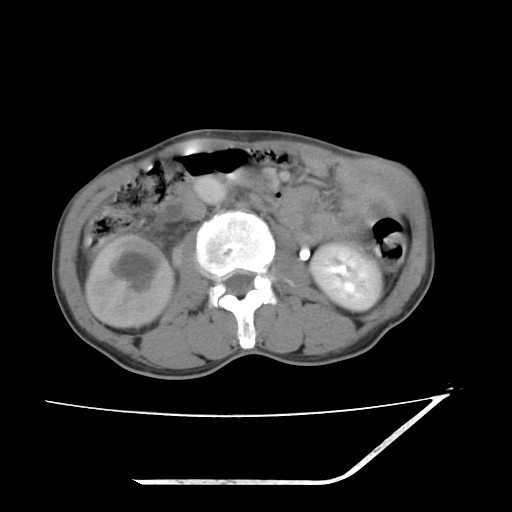

平扫

增强

考虑右肾盂癌,肾动脉受侵,右肾功能减退,右肾盂输尿管积水,管壁增厚,考虑种植转移,应该把下面扫完的

考虑右侧肾盂癌。右侧输尿管扩张未扫描完。

右肾盂癌,肾动脉受侵,右肾盂输尿管积水,管壁增厚,考虑种植转移

右肾盂移行细胞癌并右输尿管中段转移.肾积水.

1.右侧肾盂癌伴肾盂积水。

2.肾脏功能减退,原因有:(1)肾动脉受侵。(2)肾静脉受侵(3)肾积水,等。本例,肾动脉显影较好,但受压明显;肾静脉无明显显示,受压或静脉癌栓,下腔静脉腔内未见明显充盈缺损。

3.右侧上段输尿管扩张,原因:(1)积水所致;(2)种植。